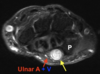

T2 FS, Hiperseñal y agrandamiento nervio ulnar.

57